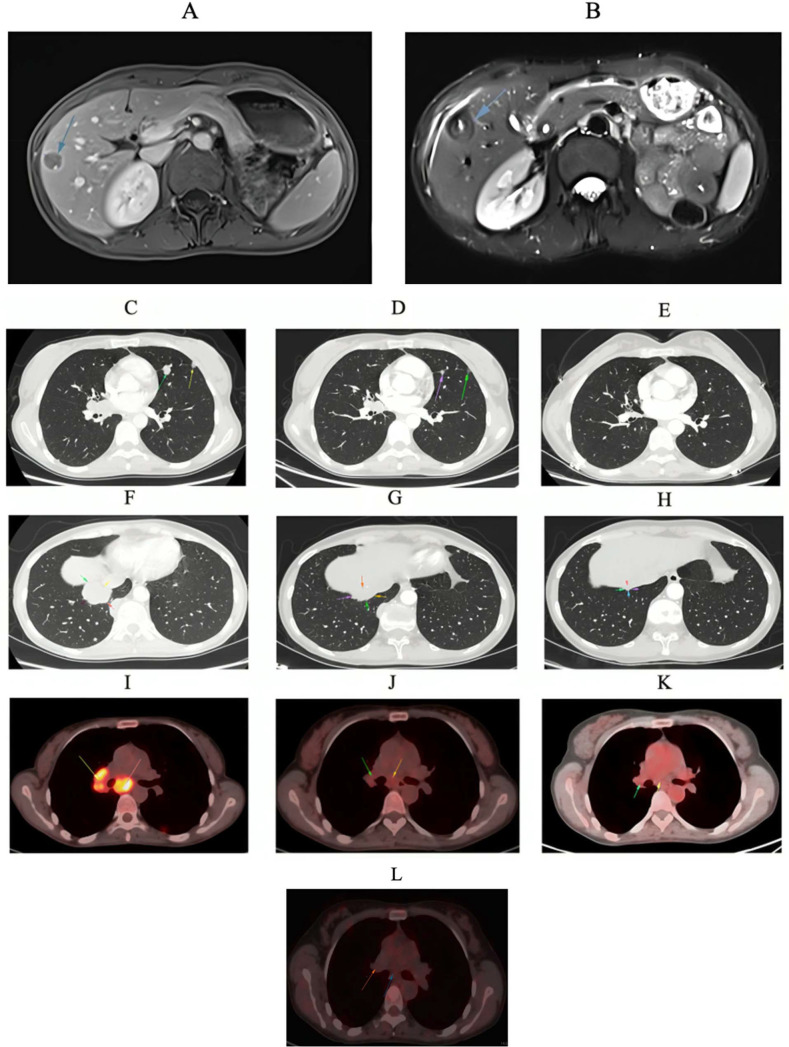

Comprehensive genomic profiling (CGP) and the subsequent discussions in molecular tumor boards (MTBs) are becoming an integral part of personalized cancer care. The patient with metastatic renal cell carcinoma (mRCC) presented here demonstrated an absence of a favorable response accompanied by adverse events after receiving dual immunotherapy with nivolumab plus ipilimumab in combination with a poly (adenosine diphosphate-ribose) polymerase inhibitor, niraparib. This determination was made based on the initial CGP report and the initial MTB. Following the progression of the disease and the emergence of immune-related adverse events, a second CGP was conducted, and several subsequent MTBs were held. The decision was made to transition the patient's treatment to temsirolimus plus bevacizumab, with the rechallenge of immunotherapy with pembrolizumab. The response evaluation revealed a complete radiographic and molecular response. This case study underscores the mounting significance of precision oncology in the management of mRCC, thereby suggesting that mammalian target of rapamycin inhibitor may augment the efficacy of immunotherapy in select patients based on their genomic findings. A digital poster of this case is included in the supplemental materials.